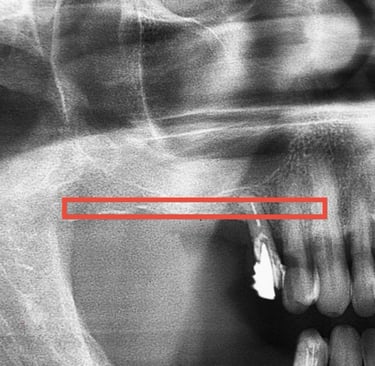

O planejamento da cirurgia dos dentes do siso normalmente é realizado por meio de tomografias computadorizadas. Elas permitem visualizar com precisão a localização do canal mandibular (seta), cuja lesão durante a cirurgia pode causar complicações neurossensoriais e hemorragias, reforçando a importância de um bom planejamento cirúrgico.